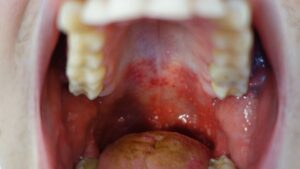

This is when diagnosis becomes clear. Small red spots appear on the tongue, gums, and inside the cheeks—particularly toward the back of the mouth near the throat. Within 24 hours, these spots evolve into painful ulcers that look like small white or gray circles with red borders. Some children develop just a few sores; others may have a dozen or more.

The pain from mouth sores often peaks during this phase. Your child may refuse favorite foods, spit out liquids, drool excessively, or cry when trying to swallow. Younger children who can’t articulate the pain might simply refuse to eat or drink entirely, which raises dehydration risk quickly. The fever may persist or begin to subside—there’s variation here among children.

Around the same time mouth sores emerge, you might notice the first signs of the characteristic rash. Small red spots begin appearing on the palms of the hands and soles of the feet. These spots are usually flat initially and may be easy to overlook, especially in children with darker skin tones.